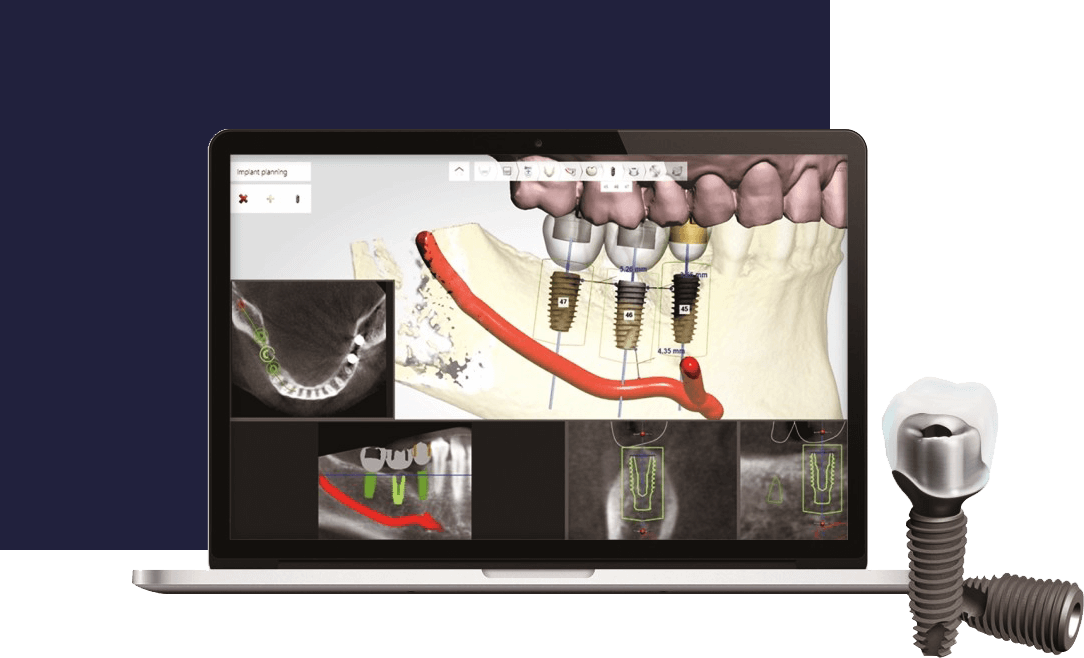

3차원 모의수술을 통한

세밀한 임플란트 식립

데오플란트치과는 임플란트 식립을 위해 환자의 3차원 CT자료를 이용한

모의수술을 진행하여 보다 안전하고 세밀한 수술을 진행 할 수 있습니다.

3D-CT를 이용한 정밀진단

3D-CT를 이용해 치아의 골조직, 주변 치아와의 거리, 각도 등을 3차원으로 파악합니다.